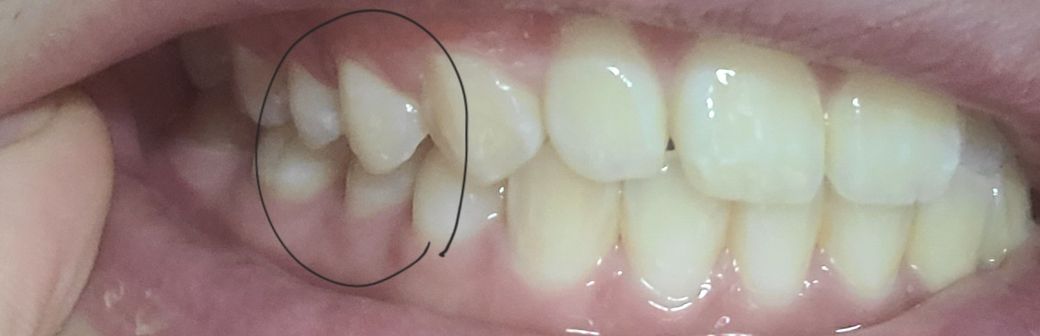

제일 위 첫번째 사진에서 윗니 1개(측절치)가 아랫니(측절치) 보다 안쪽으로 들어가 있어 정상 치아 교합이 아닙니다

왼쪽이 제1소구치쪽부터 교합이 아주 이상적인 교합은 아닙니다. 또한, 오른쪽 2번째 치아는 원래 위 치아가 아래치아를 덮어야하는데, 그렇지 않고 치아끼리 바로 닿습니다. 이 경우 치아에 무리가 갈 수 있습니다.

하지만 사진과 같이 오른쪽 2번째 윗니와 아랫니가 절단교합이 되어 있으면 치아가 다 내려오지 않아서 공간이 보일수 있어요.